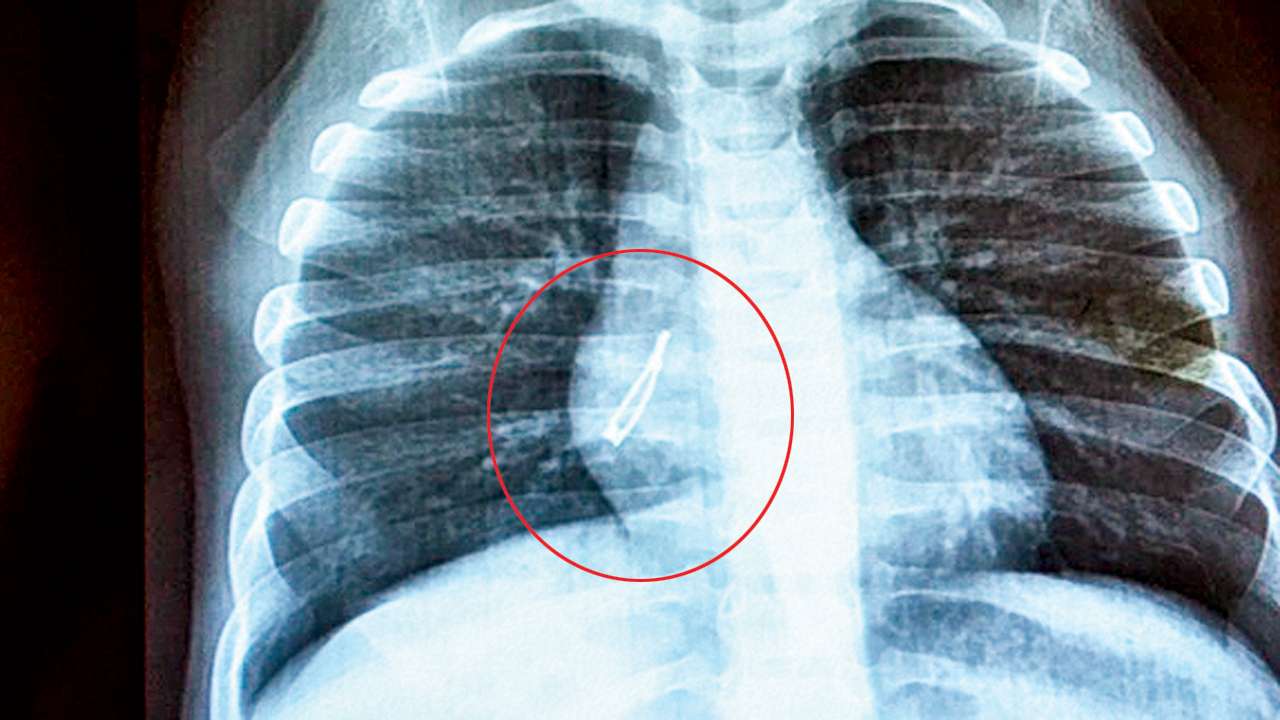

And the testing folder contains 234 normal and 390 pneumonia images. The chair is easily adjusted up and down. 77/2.5a a use automatic exposure control (500 speed for chest/abdomen, else 400 speed at specified kvp when practical). And the testing folder contains 234 normal and 390 pneumonia images. The chest radiograph is one of the most commonly requested radiographic examinations in the assessment of the pediatric patient.depending on the patients� age, the difficulty of the examination will vary, often requiring a specialist trained radiographer familiar with a variety of distraction and immobilization techniques.

The chest radiograph is one of the most commonly requested radiographic examinations in the assessment of the pediatric patient.depending on the patients� age, the difficulty of the examination will vary, often requiring a specialist trained radiographer familiar with a variety of distraction and immobilization techniques. The chest radiograph is one of the most commonly requested radiographic examinations in the assessment of the pediatric patient.depending on the patients� age, the difficulty of the examination will vary, often requiring a specialist trained radiographer familiar with a variety of distraction and immobilization techniques. The chair rotates, quickly positioning for different views. The initial view is from the front, and the second is a side view. An echocardiogram is done to confirm the diagnosis.